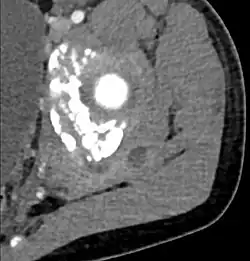

| Transverse T2 magnetic resonance imaging section through the hip region showing abscess collection in a patient with pyomyositis. | |

CT exam showing a multiloculated fluid collection in the left gluteus minimus muscle found to be a staph aureus pyomyositis in a 12-year-old healthy boy.